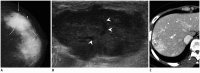

Breast metastases from extramammary malignancies are uncommon. The most common sources are lymphomas/leukemias and melanomas. Some of the less common sources include carcinomas of the lung, ovary, and stomach, and infrequently, carcinoid tumors, hypernephromas, carcinomas of the liver, tonsil, pleura, pancreas, cervix, perineum, endometrium and bladder. Breast metastases from extramammary malignancies have both hematogenous and lymphatic routes. According to their routes, there are common radiological features of metastatic diseases of the breast, but the features are not specific for metastases. Typical ultrasound (US) features of hematogenous metastases include single or multiple, round to oval shaped, well-circumscribed hypoechoic masses without spiculations, calcifications, or architectural distortion; these masses are commonly located superficially in subcutaneous tissue or immediately adjacent to the breast parenchyma that is relatively rich in blood supply. Typical US features of lymphatic breast metastases include diffusely and heterogeneously increased echogenicities in subcutaneous fat and glandular tissue and a thick trabecular pattern with secondary skin thickening, lymphedema, and lymph node enlargement. However, lesions show variable US features in some cases, and differentiation of these lesions from primary breast cancer or from benign lesions is difficult. In this review, we demonstrate various US appearances of breast metastases from extramammary malignancies as typical and atypical features, based on the results of US and other imaging studies performed at our institution. Awareness of the typical and atypical imaging features of these lesions may be helpful to diagnose metastatic lesions of the breast.